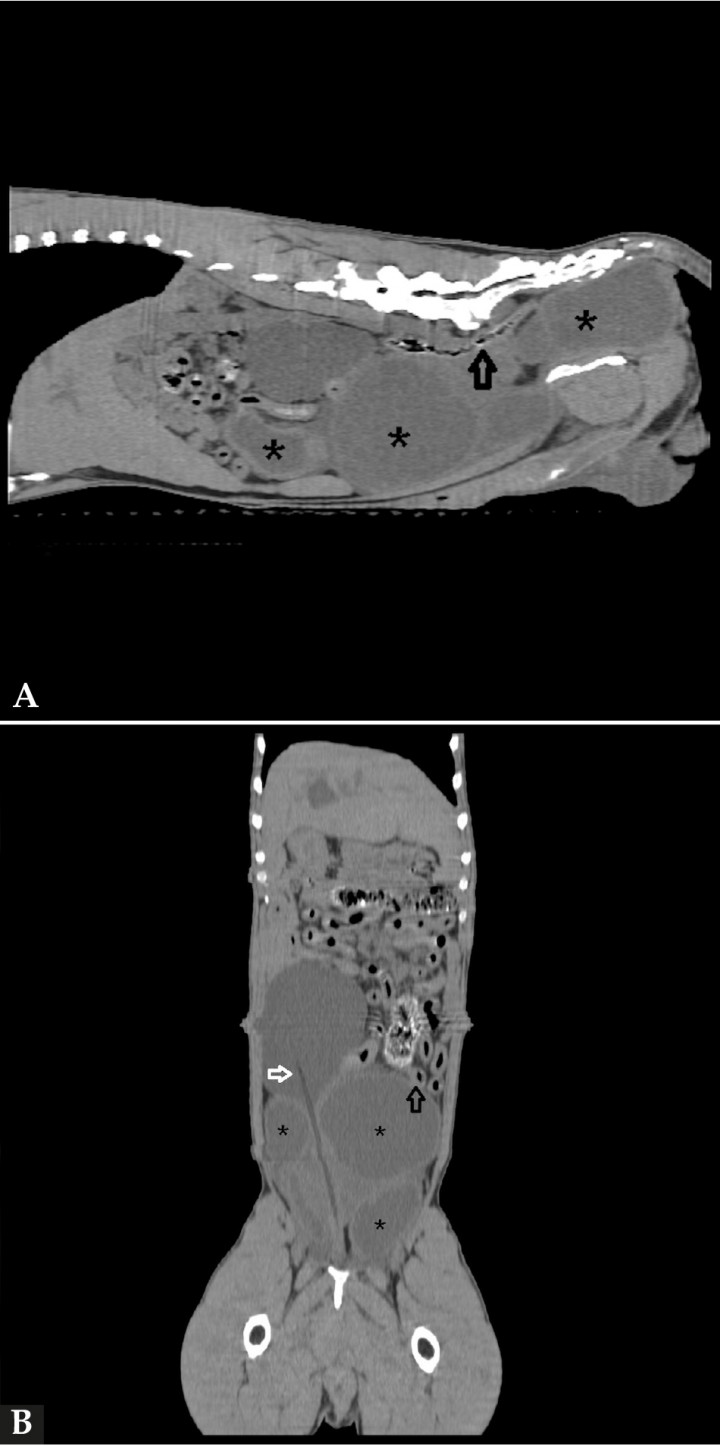

Para caracterizar estos hallazgos y plantear una cirugía, se realizó una tomografía computarizada (TC) de cavidad abdominal con fases de pre y poscontraste. Se realizó con el paciente sondado con catéter urinario para facilitar la localización de la vejiga. En el estudio de TC se confirmó la presencia de múltiples quistes que presentaban unas dimensiones de 11,5 x 7,5 cm CrCd, 17 x 9 cm DV y 11 x 9 cm LL, respectivamente, siendo más grandes que en el estudio ecográfico anterior y produciendo un desplazamiento marcado de las asas intestinales y el colon, así como el riñón derecho al cual la vejiga comprimía y desplazaba dorsalmente. Otros hallazgos fueron el aumento del ganglio linfático ilíaco medial izquierdo y la próstata aumentada de tamaño y con textura heterogénea (Fig. 4). En base a las imágenes obtenidas, el diagnóstico presuntivo fue de prostatitis y presencia de quistes paraprostáticos con desplazamiento de uno de ellos hacia la zona perineal izquierda y herniación del mismo.

<p>Imágenes de tomografía computarizada. (<strong>A</strong>) Reconstrucción en plano sagital en ventana de tejidos blandos. Se visualizan los quistes paraprostáticos (asteriscos) y el desplazamiento del colon (flecha negra) (<strong>B</strong>) Reconstrucción en plano dorsal en ventana de tejidos blandos. Diferenciamos los quistes paraprostáticos (asteriscos) de la vejiga de la orina con presencia del catéter urinario (flecha blanca). Además se evidencia el desplazamiento de las asas intestinales (flecha negra).</p>

Figura 4

Imágenes de tomografía computarizada. (A) Reconstrucción en plano sagital en ventana de tejidos blandos. Se visualizan los quistes paraprostáticos (asteriscos) y el desplazamiento del colon (flecha negra) (B) Reconstrucción en plano dorsal en ventana de tejidos blandos. Diferenciamos los quistes paraprostáticos (asteriscos) de la vejiga de la orina con presencia del catéter urinario (flecha blanca). Además se evidencia el desplazamiento de las asas intestinales (flecha negra).